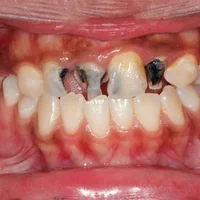

Carie profonde

Anomalie du développement structurel des dents

Amélogenèse imparfaite